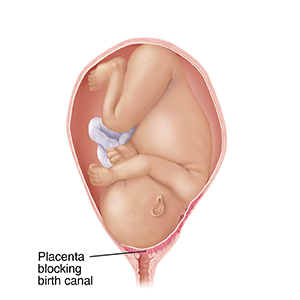

Placenta previa.Placenta blocks the cervix.